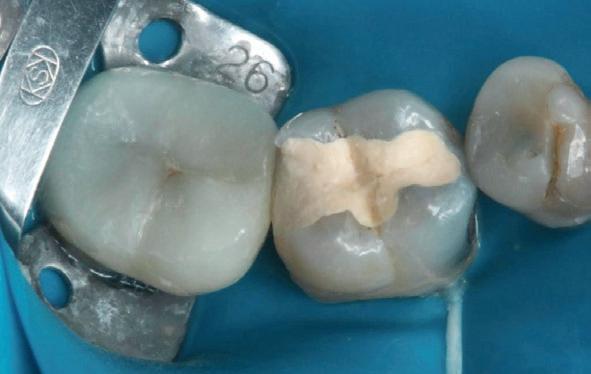

Wees niet spaarzaam met het wegnemen van aanwezig restauratiemateriaal

Misschien wel het belangrijkste onderdeel van de wortelkanaalbehandeling is de opening. Dit is de toegang tot het kanaalstelsel. Voldoende toegang maakt dat de wortelkanalen gevonden - en daarna - goed geprepareerd, gereinigd en gevuld kunnen worden. Anders gezegd, een te kleine of verkeerd geplaatste opening maakt een wortelkanaalbehandeling onnodig moeilijk en verkleint de kansen op een succesvolle behandeling aanzienlijk. Een te kleine opening is een mogelijke oorzaak van instrumentbreuk. Hoe zorg je voor een goede opening? Aan de hand van een casus die naar mij is verwezen, laat ik zien hoe je een goede opening maakt en wat de gevolgen zijn van een te kleine en verkeerd geplaatste opening.

Voordat je aan een wortelkanaalbehandeling begint, zorg je voor (of maak je) een goede beginfoto waar het te behandelen gebitselement volledig op staat afgebeeld. Deze foto geeft essentiële informatie: de grootte van de pulpakamer en de ligging ervan; het aantal en de vorm van de wortels en de breedte van hun wortelkanalen en de lengte van de wortels. Hiermee kan je de DETI-score bepalen en de moeilijkheidsgraad inschatten. De grootte en de ligging van de pulpakamer op de röntgenfoto in combinatie met de ideale anatomische vorm, zoals in foto 1 is aangegeven, bepaalt de uiteindelijke vormgeving van de opening. Bij de molaren liggen de kanaalingangen in de buurt van de knobbeltoppen. Als die niet meer in originele staat

(kroon, restauratie) zijn, kan je ook de wortel gebruiken. Soms moet je net subgingivaal sonderen, maar de kanaalingang ligt in het middel van de wortel. Als je die plek visualiseert en projecteert op je opening, boor je de goede kant op. Nog een tip: wees bij het openen niet spaarzaam met het wegnemen van aanwezig restauratiemateriaal (wees wél spaarzaam met het onnodig wegnemen van tandweefsel).

De casus

De verwijzend tandarts is bezig om een wortelkanaalbehandeling uit te voeren in gebitselement 27. Er zijn vier kanalen gevonden, maar helaas breekt er in het mesiobuccale kanaal (MB 1) een WaveOne vijltje af, maat geel (foto 2). Het lukt de tandarts niet om

3. De opening is vrij klein gekozen. In rood is de ideale opening aangegeven, de tandarts had veel meer restauratiemateriaal mogen wegnemen.

Als ik de patiënte zie, valt me op dat de opening die de tandarts gemaakt heeft, nogal klein is (foto 3). Eigenlijk is daar niet zoveel reden toe; als ik een ideale opening inteken (in rood), dan loopt een groot deel door restauratiemateriaal. Overwogen kan worden om de aanwezige mesiale box met restauratiemateriaal weg te halen als dat het zicht op de pulpakamer vergroot – ik verwijs naar de tip hierboven (wees bij het openen niet spaarzaam met het wegnemen van aanwezig restauratiemateriaal).